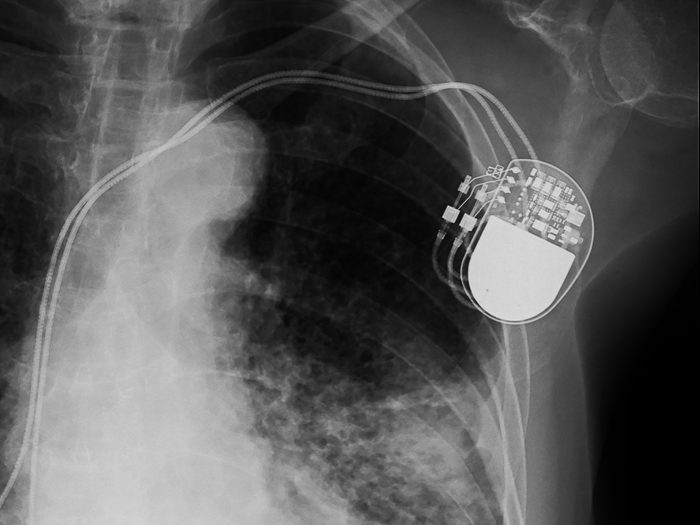

x-ray image of permanent pacemaker implant in body chest.

ChooChin/Shutterstock

Pacemaker

Called the “father of biomedical engineering” by the British Columbia Medical Journal, John Hopps came up with the idea for the pacemaker while researching ways to improve open-heart surgery. He realized an electrical impulse could regulate the heart’s pacing—and even restart it. At the National Research Council in the early 1950s, he created the first external pacemaker, which delivered an electrical pulse through a catheter inserted into the jugular vein. This would pave the way for the implantable pacemaker later on, which Hopps would benefit from himself: He had one implanted in 1984.